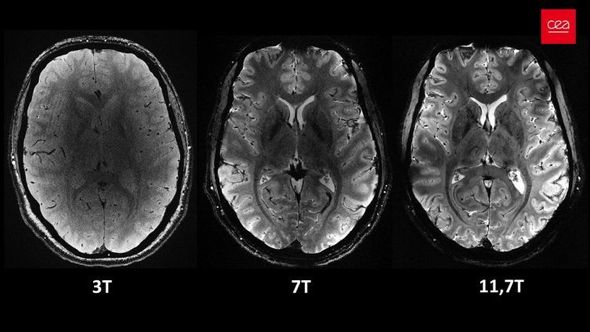

Açıqlamada qeyd olunub ki, 11,7 Tesla maqnit gücünə malik “Iseult” cihazı ilə qısa müddətdə çəkilən görüntüləri xəstəxanalarda istifadə edilən cihazlarla əldə etmək saatlar çəkə bilər.